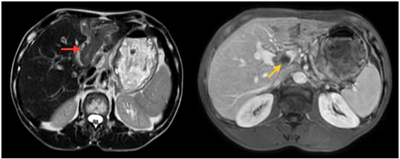

UNG THƯ BIỂU MÔ TẾ BÀO THẬN

Ung thư thận là loại ung thư thường gặp đứng thứ 14 trên toàn cầu, với hơn 430.000 ca mới được chẩn đoán vào năm 2020, và 434840 ca mắc trên toàn cầu vào năm 2022. Tỷ lệ mắc thay đổi theo khu vực địa lý, cao hơn ở châu Âu và Bắc Mỹ. Ung...